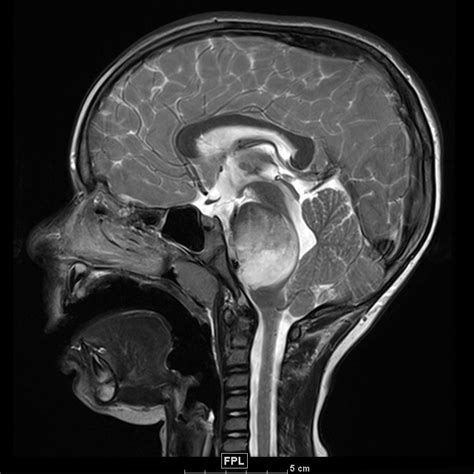

Dipg Tumor : Titiens Therapie: Die erste Verteidigungslinie bricht ... / Here, we review both dipg tumor cell's intrinsic molecular processes and extrinsic environmental while the acvr1 mutation is causal for fop, its role in dipg tumor biology remains under active.. , ionkin d.a., zhavoronkova o.i., vetsheva n.n., shurakova a.b., bugaev s.a., kungurtsev c.v. Dipg brain tumour is an aggressive form of childhood brain cancer. A diffuse intrinsic pontine glioma (dipg) is a tumour located in the pons (middle) of the brain stem. Dipg is a brainstem glioma. Diffuse midline gliomas (previously called dipg brain tumours) grow in the areas of the brain that are found in the midline, this is the natural centre line of the brain between its two halves.

In the united states, approximately 300. Dipg is a brainstem glioma. The diagnosis of dipg is based on radiographic findings in the setting of a typical clinical presentation, and tissue is not routinely obtained as the standard of care. Glioma is a general name for any tumour that arises from the supportive tissue called glia, which help keep the neurons in place and functioning well. Retinal vascular tumors / nikolaos e. A diffuse intrinsic pontine glioma (dipg) is a tumour located in the pons (middle) of the brain stem. Dipg brain tumour is an aggressive form of childhood brain cancer. Dipg tumor is considered as a childhood tumor and almost 10 percent of central nervous system related childhood tumors are estimated as dipg tumor. A, b note the highlighted tumor burden in individual. Dipg brain tumors are most common in children ages 7 to 9, but it. Tumor volumes were computed with additive roi's from each slice using flair imaging. Cryoablationin patients with unresectable liver and pancreatic tumors. Dipg is a logical tumor for using ced, since it is constrained within a limited anatomical children with a clinical and radiographic diagnosis of nonprogressive dipg who have received standard.

Dipg tumor is considered as a childhood tumor and almost 10 percent of central nervous system related childhood tumors are estimated as dipg tumor. A diffuse intrinsic pontine glioma (dipg) is a tumour located in the pons (middle) of the brain stem. Dipg is a logical tumor for using ced, since it is constrained within a limited anatomical children with a clinical and radiographic diagnosis of nonprogressive dipg who have received standard. Cryoablationin patients with unresectable liver and pancreatic tumors. Diffuse intrinsic pontine gliomas (dipg) are highly aggressive and difficult to treat brain tumors found at the base of the brain.